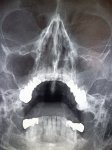

IMG20251208141427.jpg

Где пиздецома?

>>327474923

Ателектаз слева?

Аноним 09/12/25 Втр 08:22:33 #42 №327475511

Хм, так понимаю увеличены сердце и магистральные сосуды, которые дают такую мощную тень?

Аноним 09/12/25 Втр 08:27:51 #47 №327475609

>>327475506

И опухоль тож, там рак желудка первичный

Сердце почти нк расширено, там рак с первичным очагом в желудке.

Аноним 09/12/25 Втр 08:30:34 #49 №327475664

>>327475631

Центральный рак лёгкого справа?

>>327475724

Метастазы, из желудка

Я про то, на снимке сами метастазы где? В районе бронхов справа?

Аноним 09/12/25 Втр 08:39:09 #62 №327475829